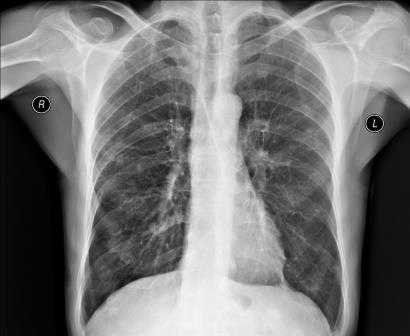

Рентгенография грудной клетки - это метод диагностики, позволяющий получить изображение органов грудной полости с помощью облучения рентгеновыми лучами. Различные ткани организма в зависимости от своей плотности по-разному пропускают рентгеновы лучи, а значит, по-разному отображаются на снимке (рентгенограмме).

Рентген грудной клетки дает возможность изучить костные структуры (ребра, грудину, позвоночник), легкие, плевру, бронхи и трахею, сердце и средостение, а также оценить состояние мягких тканей этой области.

Прежде всего, рентген грудной клетки используется для диагностики заболеваний легких.

Рентген грудной клетки способен выявить:

- присутствие в легких очагов воспаления, в том числе характерных для таких заболеваний как пневмония и туберкулёз;

- наличие опухолевых образований и отеков, которые могут быть следствием сердечной недостаточности;

- наличие патологических скоплений газов и жидкостей;

- скопление жидкости в околосердечной сумке, увеличение размера сердца, аорты и лимфатических узлов;

- инородные предметы в легких, пищеводе и дыхательных путях.